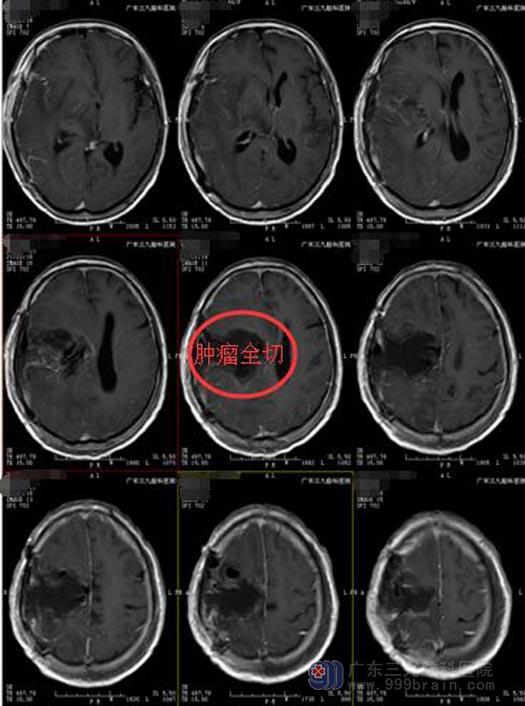

综合考虑肿瘤位置、大小、侵入因素及患者之后的语言运动功能,详细讨论病情后,决定在麻醉唤醒下行胶质瘤二次切除术,术前导航定位肿瘤范围,术中给予唤醒麻醉,电生理监测,电刺激定位语言、运动功能区,定位肿瘤区域,避开功能区,顺利切除肿瘤。张女士术后头痛缓解,语言功能完好,可自行活动。

手术后